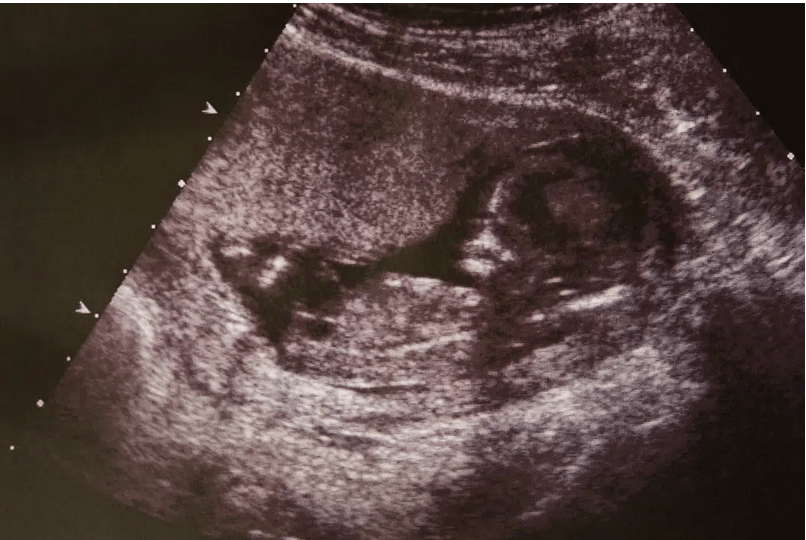

Aunque el bebé no nacido está dentro de la madre, él es un ser humano distinto, como se puede ver a continuación: